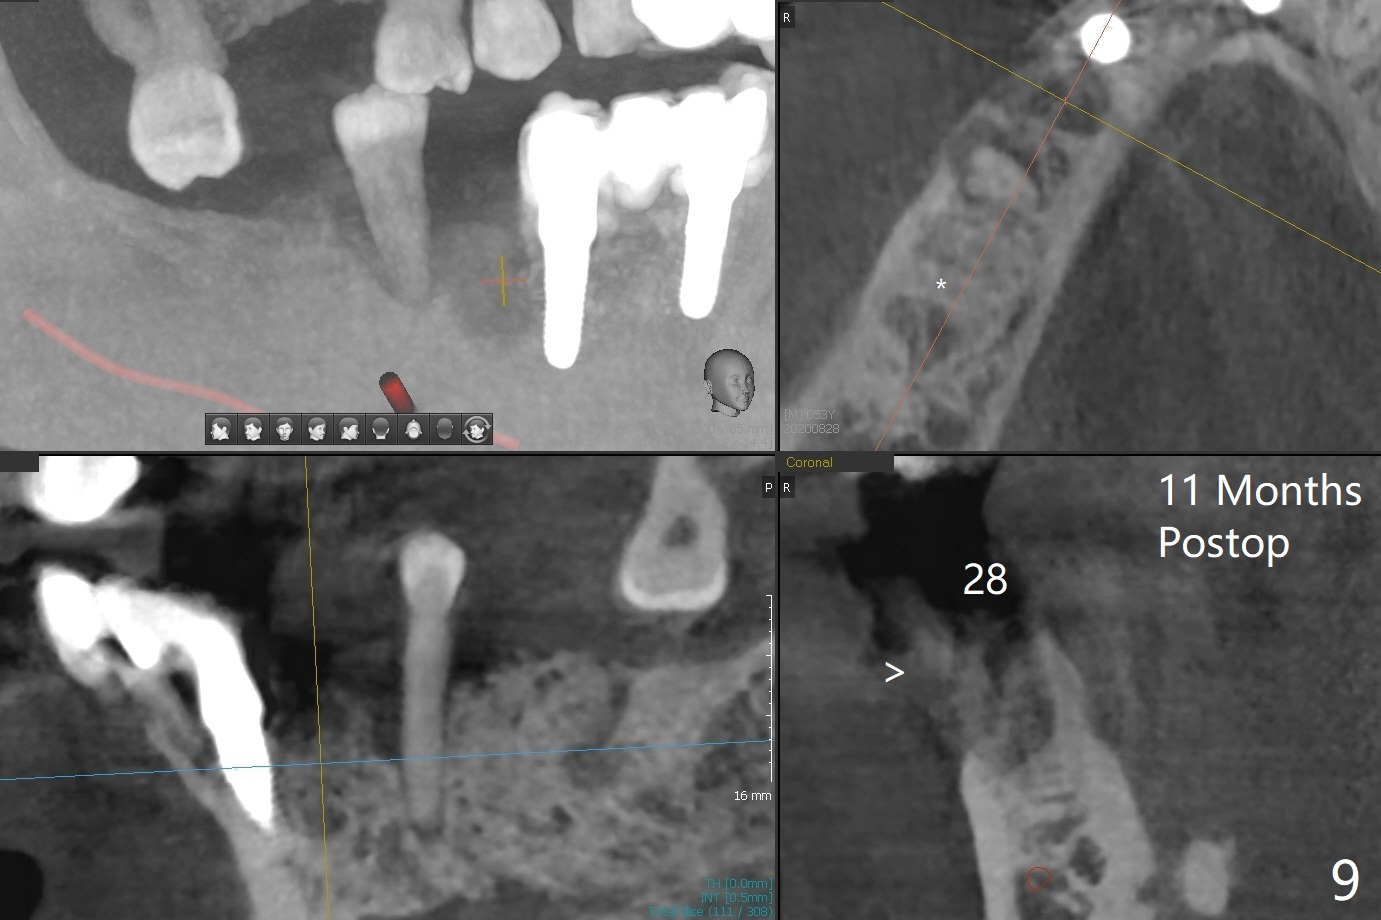

A 52-year-old man with poor dentition has concept of socket preservation when he wants extraction at #30. There is bone loss with the presence of the septum (Fig.1,2 *). Mixture of Vanilla graft and Osteogen is packed around the septum (Fig.3). With blood supply from the septum, the allograft should be more efficiently converted to the native bone than without the septum. The socket is closed with Osteogen plug and suture (Fig.4). In fact the bone height increases by 2.4 mm over the septum 11 months postop (Fig.5,6). In contrast there is apparently no bone regeneration in the socket of #28 four months postop without bone graft (Fig.7). Implant to be placed in the "empty" socket may fail. With bone graft, the ridge at #30 is higher than the surrounding bone 18 months postop (Fig.8 ^) with formation of the cortex on the top of the alveolus <). The average bone density is 1500 units. In contrast, without bone graft, the buccal plate at #28 is missing 11 months postop (Fig.9 >) with average bone density at 500 units. The implant at #28 should be long to engage to the apical native bone (Fig.10) with incision in case of need for bone graft. Sticky bone will be placed mesial to #29.